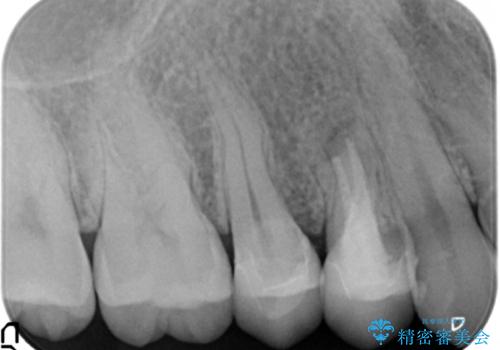

術後は瘻孔、圧痛、打診痛も消失し、根尖病変の縮小もみられました。経過良好です。

- 約27万円(税別) 右上45 emaxクラウン、仮歯 右上4 精密根管治療、ファイバーコア費用は治療当時の料金となります